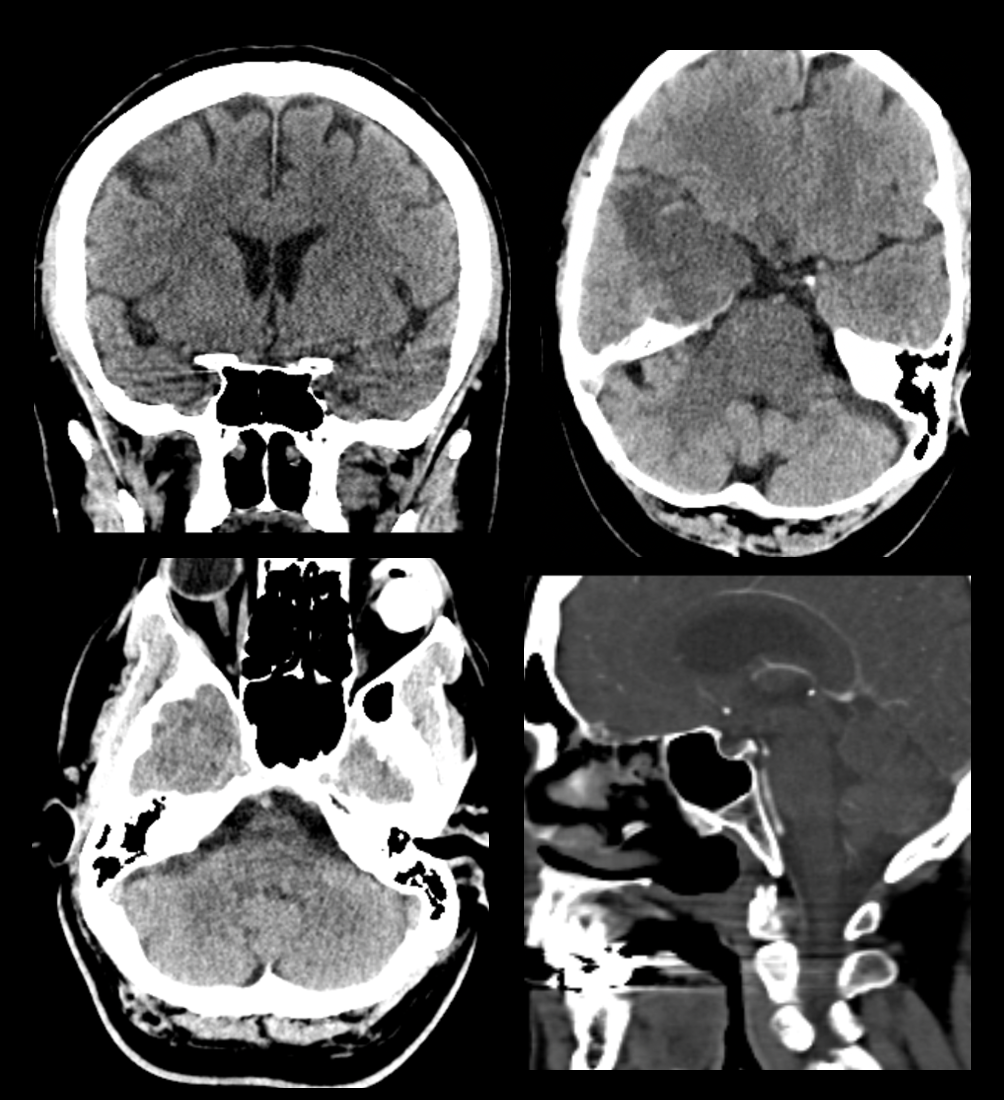

Master the Basics of CT Head intrepretation

Are you an emergency medicine physician looking to enhance your CT head interpretation skills? Join me, a passionate radiologist with a decade of experience, on a transformative journey. This course is designed to help you read images on your busy shifts with more knowledge and confidence.

Beam Hardening Artifact

Beam Hardening Artifact - What you Need to Know

Temporal lobe - Artifact or Pathology?

Posterior fossa - Artifact or Pathology?